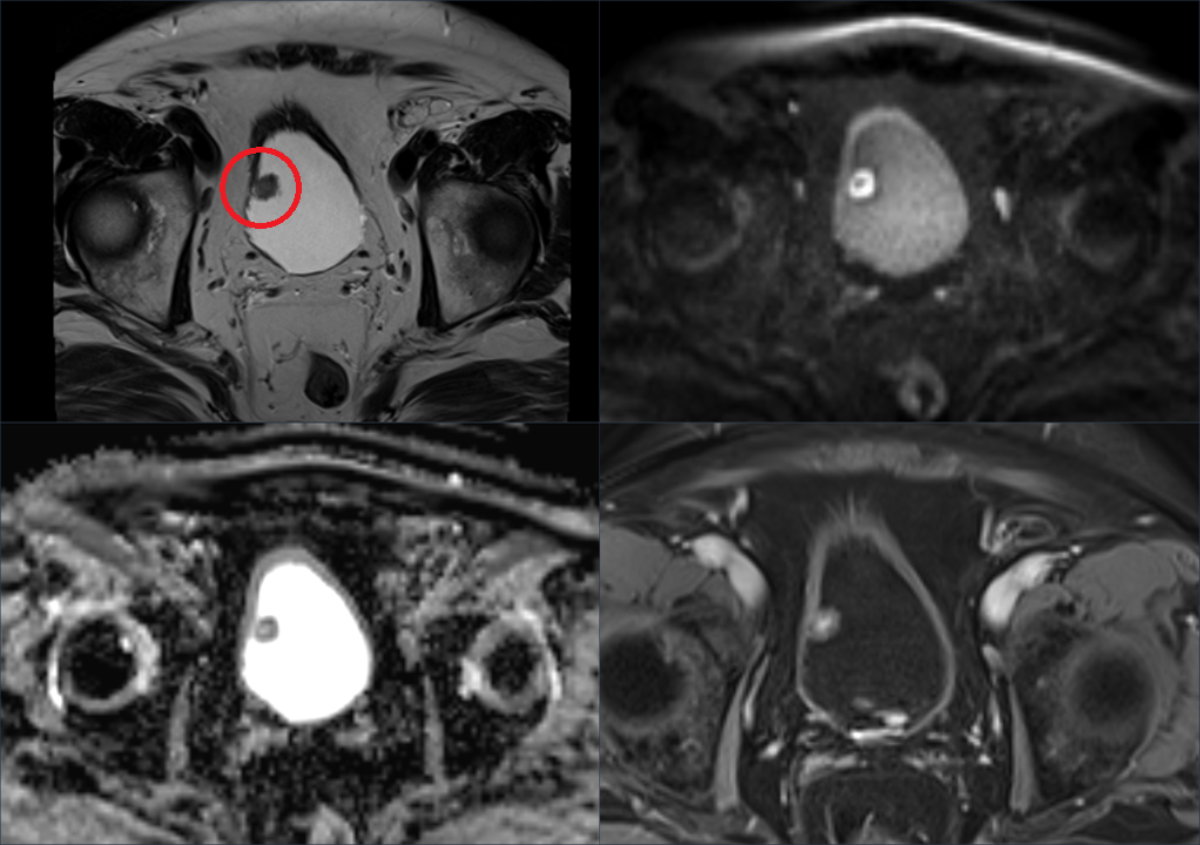

Bildgebung: MRI der Harnblase

Die multiparametrische Magnetresonanztomographie (MRI) der Harnblase liefert uns detaillierte Informationen über Lokalisation und Ausdehnung von Blasentumoren.

Beispiel einer multiparametrischen MRI der Harnblase. Vier unterschiedliche Sequenzen (Parameter) zeigen die Lokalausdehnung eines Harnblasenkarzinoms am rechten Harnblasendach (roter Kreis, oben links).

Ein MRI der Harnblase ermöglicht uns die Beurteilung von Tumorgrösse, Infiltrationstiefe in die Blasenwand und umgebendes Gewebe, sowie das Vorhandensein von Lymphknotenmetastasen. Diese Bildgebung unterstützt die Ärztinnen und Ärzte bei der Stadieneinteilung und der Auswahl geeigneter Behandlungsoptionen.

Darüber hinaus kann die MRI in der Langzeitnachsorge nach abgeschlossener Behandlung zur frühzeitigen Erkennung von Rückfällen oder Metastasen eingesetzt werden.